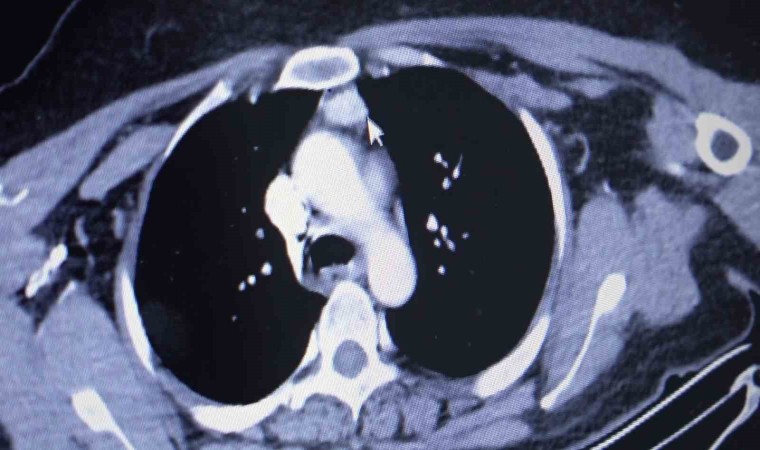

Amasya’da ayak tabanındaki yanma ve kaşıntıların giderek artması şikayetiyle hastaneye başvuran kadına, 100 binde 1 kişide görülen bir hastalığın teşhisi konuldu. Vücuda kalsiyum salgılayıp düzeyini kontrol eden 4 paratiroid bezinden biri, normalde olması gereken boyun yerine hastanın kalbinin üstünde bulundu. 3,4 kat büyümesiyle hastanın sağlığını tehdit eden kitle, başarılı bir ameliyatla alındı.

Amasya’nın Göynücek ilçesine bağlı Karaşar köyünde yaşayan evli ve 3 çocuk annesi Emine Şahin’in Amasya Üniversitesi Sabuncuoğlu Şerefeddin Eğitim ve Araştırma Hastanesi’nde yapılan kontrollerinde normalde boyun kısmında olan paratiroid bezlerinizden biri göğüs kafesi içinde kalbe yakın bir noktada tespit edildi. Amasya Üniversitesi Tıp Fakültesi Dekanı Prof. Dr. Cafer Polat, Dr. Öğretim Üyesi Suat Evirgen ve göğüs cerrahisi ekibinin katılımıyla gerçekleştirilen ameliyatla kitle vücuttan çıkarıldı. 50 yaşındaki hasta şikayetlerinden kurtularak sağlığına kavuştu.

Dr. Evirgen, “100 binde 1 kişide ender rastlanan ve bölgemizde ilk defa yapılan bir ameliyatı gerçekleştirdik. Çünkü Emine hanımın paratiroid adenomu normalde bulunması gereken boyun bölgesinde değil de göğüs boşluğu içindeydi. Bu bezler vücuda hormon salgıladığı için kemik erimesine, kanda kalsiyum artışına sebep oluyor. Bu tür hastalardaki şikayetlerin sebebi de zaten bu bezlerin büyümesidir” diye konuştu.